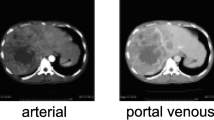

Contrast-enhanced CT dataset of 40 patients (n = 40; M:F = 5:3; age = 25–55 years) with three groups of subjects: healthy (n = 14), cirrhosis (n = 12) and cirrhosis with HCC (n = 14), were retrospectively analyzed in this study. A novel method for the automatic 3D segmentation of liver using modified region-growing segmentation technique was developed and compared with the state-of-the-art deep learning-based technique. Further, histogram parameters were calculated from segmented CT liver volume for classification between healthy and diseased (cirrhosis and HCC) liver using logistic regression. Multi-phase analysis of CT images was performed to extract 24 temporal features for detecting cirrhosis and HCC liver using support vector machine (SVM).

Lee JH, Lee JM, Kim SJ et al (2012) Enhancement patterns of hepatocellular carcinomas on multiphasic multidetector row CT: comparison with pathological differentiation. Br J Radiol 85:e573–e583. https://doi.org/10.1259/bjr/86767895

Marrero JA, Ahn J, Reddy RK (2014) ACG clinical guideline: the diagnosis and management of focal liver lesions. Am J Gastroenterol 109:1–20. https://doi.org/10.1038/ajg.2014.213